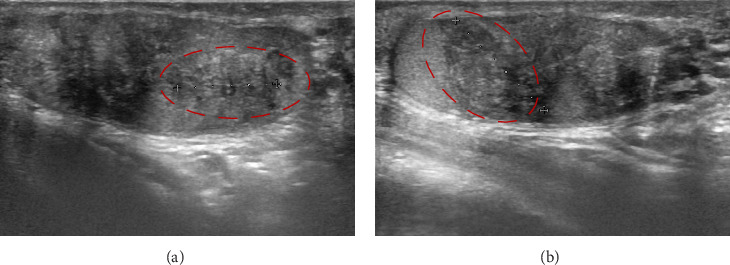

Congenital adrenal hyperplasia (CAH) due to 11-beta-hydroxylase deficiency (11β-OHD) is the second most common steroidogenesis impairment in European populations, characterized by hypertension, hypokalemia, infertility, hyperandrogenism, and genital ambiguity in females. We present the case of a biological male patient with 11β-OHD CAH who developed resistant hypertension, along with massive adrenal enlargement and testicular adrenal rests due to inadequate disease control while on dexamethasone treatment, compounded by drug interactions with his antiepileptic therapy. As the patient was reluctant to switch to a three-times-daily hydrocortisone regimen, he was transitioned to dual-release hydrocortisone, resulting in progressive improvement of most of his symptoms. This case highlights the importance of tailored therapy, particularly in rare diseases.

由11- β-羟化酶缺乏症(11 - β- ohd)引起的先天性肾上腺皮质增生症(CAH)是欧洲人群中第二常见的类固醇生成障碍,其特征是女性高血压、低钾血症、不孕症、高雄激素症和生殖器模糊。我们报告了一例患有11β-OHD CAH的男性生物学患者,他在接受地塞米松治疗期间由于疾病控制不充分而出现了顽固性高血压,并伴有大量肾上腺肿大和睾丸肾上腺衰竭,加上药物与抗癫痫治疗的相互作用。由于患者不愿改用每日三次的氢化可的松治疗方案,因此改用双释氢化可的松治疗,导致其大部分症状逐渐改善。该病例突出了量身定制治疗的重要性,特别是在罕见疾病中。